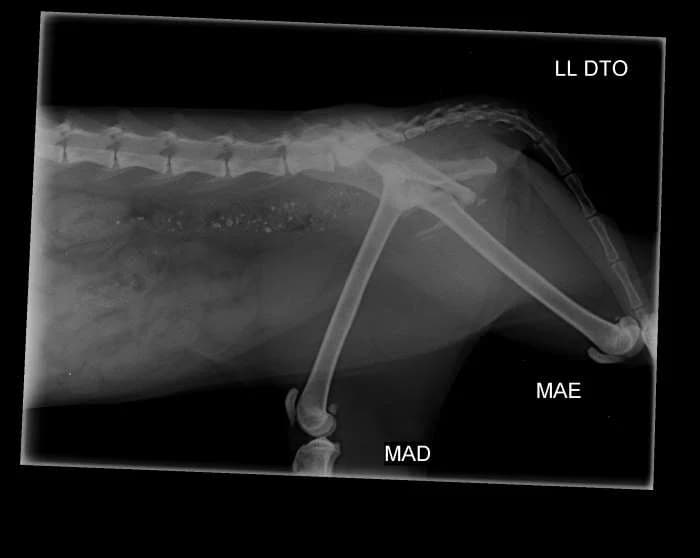

Gena was found run over at Quinta do Conde. There are several fractures in the basin. It needs a lot of rest. We still don't have confirmation that he'll be operated. She's doing antibiotics, anti-inflammatory drugs and painkillers. Gena's a sweetheart! Gena's shy, but she's ready for adoption! Gena is sponsored by António M.